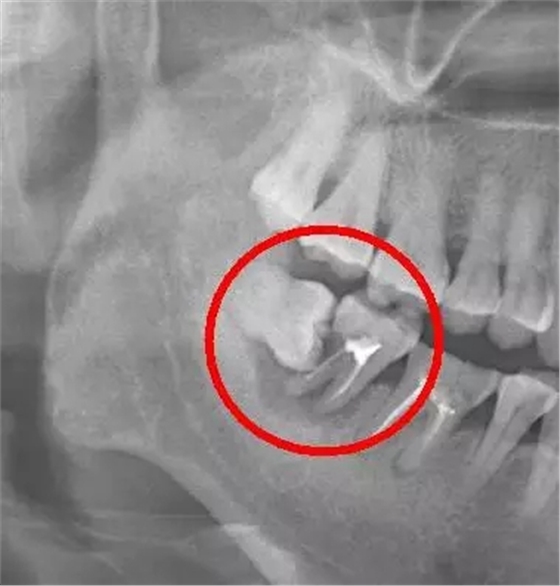

阻生智齒中典型的“秀恩愛,死得快”型,智齒因為萌出空間不足,造成傾斜阻生,斜靠在旁邊的牙齒上,把旁邊好好的鄰牙給直接頂壞掉。

阻生智齒的幾種常見類型

口說無憑,上病例。來看下面這例

這種情況就因為沒及時拔除智齒,最終的結(jié)果就是把鄰牙也拖下水,兩顆牙齒一起報銷,旁邊的第二恒磨牙本來就容易因為清潔不徹底齲壞的好么,還要無端被拖著陪葬,真是生存不易。更慘的是,鄰牙拔除之后,還必需要裝上一顆種植牙補上(我會告訴你裝一顆種植牙花費上萬是很正常的么),得不償失?。?!

下面這例又是一個悲傷的故事:

需要特別注意的是,鄰牙病變具有一定的隱蔽性,通常的情況是可能旁邊牙齒已經(jīng)被頂壞了,患者還沒有任何感覺,這就需要拍一張口腔 X 光片才能進行準確的診斷。